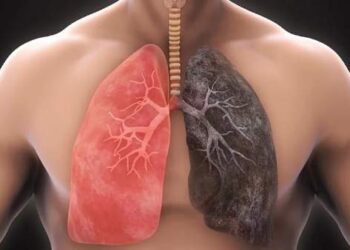

۵. افراد با مصرف سیگار و مواد الکلدار

افرادی که سیگار مصرف میکنند، احتمال بروز عفونت دهانی در این افراد افزایش پیدا میکند. این افراد در صورت انجام ایمپلنت فوری در تهران باید مصرف سیگار را ترک کنند. چراکه میزان نیکوتین موجود در سیگار روند ترمیم شدن پایه ایمپلنت را کند میکند. از طرفی، افراد سیگاری در مقایسه یا افراد دیگر کمتر بهداشت دهان و دندان را رعایت میکنند که این موضوع احتمال شکست ایمپلنت را افزایش میدهد.